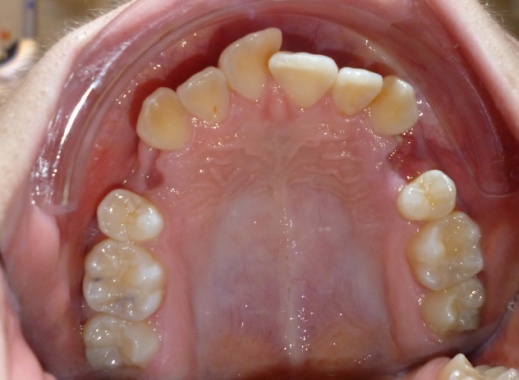

1 - Arcades dentaires avant-après

Les photos montrent un encombrement dentaire important associé à une classe II dentaire. Les extractions de prémolaires ont été décidées non seulement pour créer la place nécessaire à l’alignement, mais aussi pour corriger le décalage de classe II. Le résultat final illustre qu’un plan de traitement bien réfléchi peut répondre simultanément aux impératifs fonctionnels et esthétiques, sans compromettre l’harmonie faciale.